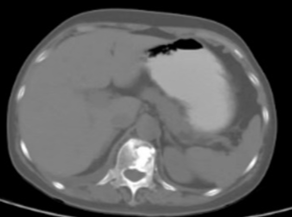

案例4:

患者左侧精索平滑肌肉瘤术后,肺转移、胸椎旁转移。CT示第7胸椎左侧附件破坏伴周围软组织肿物,考虑转移。左侧胸背部持续性放电样疼痛,向左前胸壁放射,体位受限,不能左侧卧位,并伴有因体位改变诱发疼痛加重,属于骨转移性癌痛合并癌性神经病理性疼痛。硫酸吗啡缓释片60 mg q12h按时服用及吗啡片20 mg/次处理爆发痛,NRS:6-8分。胸椎局部压痛、叩击痛阳性。癌性神经病理性疼痛单纯阿片药物治疗不满意,根据NCCN成人癌痛治疗指南,神经病理性疼痛可试用抗抑郁药和/或试用抗惊厥药,对于顽固性疼痛,考虑采用介入治疗。

本例患者采用阿片药物+抗惊厥药联合治疗后,疼痛减轻,但出现谵妄不良反应。谵妄是以认知功能损害和意识水平下降为特征的脑器质性综合征,也是晚期癌症患者最常见的精神障碍之一。在应用阿片药物治疗癌痛时出现谵妄症状,及时应用抗精神异常药物处理谵妄症状,对于引起疼痛的肋骨根部转移病灶,采用碘125粒子植入术,术后肿瘤缩小,疼痛缓解,停用阿片药物,治疗效果显著(图3)。

3A

3B

图3:3A左侧第7后肋及左附件破坏伴周围软组织肿物,3B放射性粒子治疗后2个月左7肋根肿物较前缩小